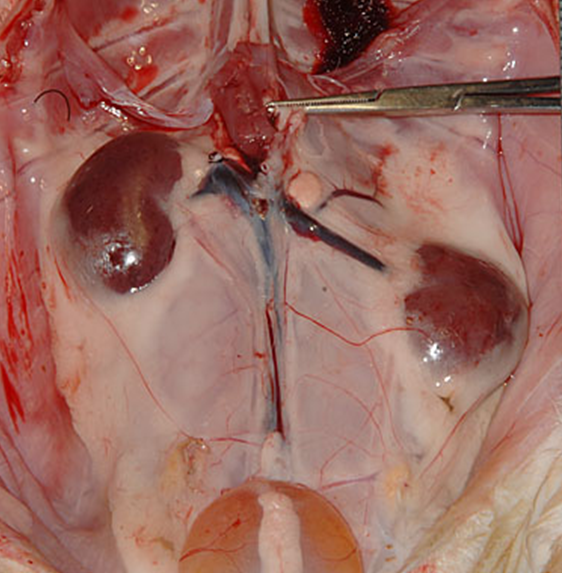

Encephalitozoon cuniculi は、腎臓と中枢神経系に親和性を持つ偏性細胞内寄生性の微胞子虫です 。この原虫による感染は飼育ウサギのコロニーに広範に蔓延しており、ペットウサギ集団における血清陽性率は38~78%と高いことが報告されています〔Škrbec et al.2023〕 。しかし、感染ウサギの多くは無症状のキャリア(不顕性感染)として生涯を過ごし、臨床疾患として発現するかは宿主の免疫状態や他疾患の有無に左右されると考えられています。腎臓はE.cuniculi の主要な標的臓器の一つです。感染が慢性化すると、腎皮質表面に境界不明瞭で不規則な陥凹が多発する点状陥凹腎(凸凹の腎臓)と呼ばれる外観を呈するとともに、特徴的な肉芽腫性間質性腎炎を引き起こすことが知られています〔Tangchang et al.2024〕。CRFの主要な原因としても指摘されています〔Sze-Yu et al. 2025〕 。

ウサギの腎不全において、超音波検査は、腎臓の大きさに加え、X線検査では評価が困難な腎実質の内部構造、皮質と髄質の境界、腎盂の状態、さらには血流(ドップラー使用時)を評価するために不可欠な診断ツールです。CRFが進行すると、腎臓は線維化や組織の萎縮により縮小(腎萎縮)し、正常より小さくなることがあります 。また、腎臓の辺縁が不整になり、ゴツゴツとした輪郭を呈することがあります 。間質の線維化、尿細管変性、鉱質沈着(石灰化)などが起こると、腎実質(特に皮質)のエコー輝度は上昇し、周囲の脾臓や肝臓と比較して白っぽく見えます 。急性腎不全では、浮腫や炎症の程度によってエコー輝度が低下することもあります 。正常なウサギでは、皮質(やや低エコー)と髄質(より低エコー)の境界は比較的明瞭に描出されます 。慢性腎不全で線維化や実質の構造破壊が進行すると、この皮質・髄質境界は不明瞭になります 。腎石灰化によるカルシウム沈着は、高エコー輝度の斑点や線状構造として描出され、強い音響陰影を伴うことがあります。また、水腎症では腎盂内部が無エコーの尿で拡張する一方、腎盂膿瘍では無エコーよりエコー輝度が高い膿によって拡張します。腎実質内に辺縁明瞭な無エコー領域(嚢胞)が単発性または多発性(多発性嚢胞腎)に見られることもあります 。腎臓腫瘤は、腎臓の形状不整、実質の不均一なエコーパターン、あるいは正常構造を破壊する腫瘤(例:リンパ腫によるびまん性の高エコーまたは低エコー浸潤)として観察されることがあります。